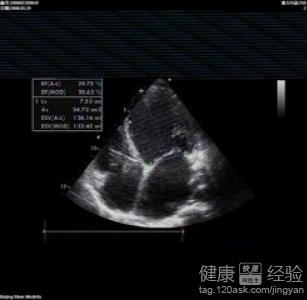

圍產期心肌病的情況是指懷孕後的婦女產生了心力衰竭等心髒疾病的症狀。引發這樣症狀的原因有很多種,主要的還是跟患者自身的免疫力系統下降、病毒感染、雙胞胎。多產或者是高血壓的情況引發的,另外患者自身如果以前有其他的心腦血管疾病的話,也是很有可能會引發這樣的症狀出現。腎髒缺鉀的情況跟身體的吸收能力、腎髒的調節能力還有外傷等有直接的關系。

1圍產期心肌病的患者是屬於非常危險的情況,這樣的情況下一般要及時的進行有效治療和控制。心力衰竭前期的治療要注意觀察患者的體征,注意補充維生素和加強營養。可以使用一些改善心髒代謝的藥物。

2患者如果出現了心髒衰竭的症狀後,要多注意休息,保證患者的身體不能有勞累感出現。飲食上不要吃含鹽分多的食物,采用利尿劑來進行治療。還可以使用洋地黃等藥物來改善患者的心髒功能。